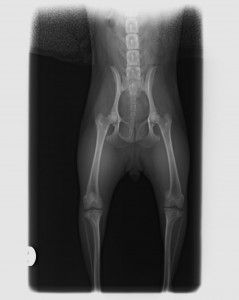

Displasia de cadera

Se trata de una enfermedad hereditaria, que se suele dar en razas como el pastor alemán, labrador, mastín, rottweiler, etc. Suele empezar a dar problemas a partir de los 7-8 meses de edad del cachorro, y es muy importante la detección precoz de la enfermedad.

El tratamiento puede ser

conservador, y si éste no funciona, pensar en un tratamiento quirúrgico. En este caso, cuanto antes hagamos la cirugía, mejor pronóstico va a tener nuestro perro.

Si lo que queremos es prevenir, es muy importante realizar radiografías si son de una raza predispuesta. Además, ofrecemos la posibilidad de realizar un Test Genético para labradores, mediante una muestra de sangre, y nos predice la capacidad de tener y transmitir la enfermedad a la descendencia.